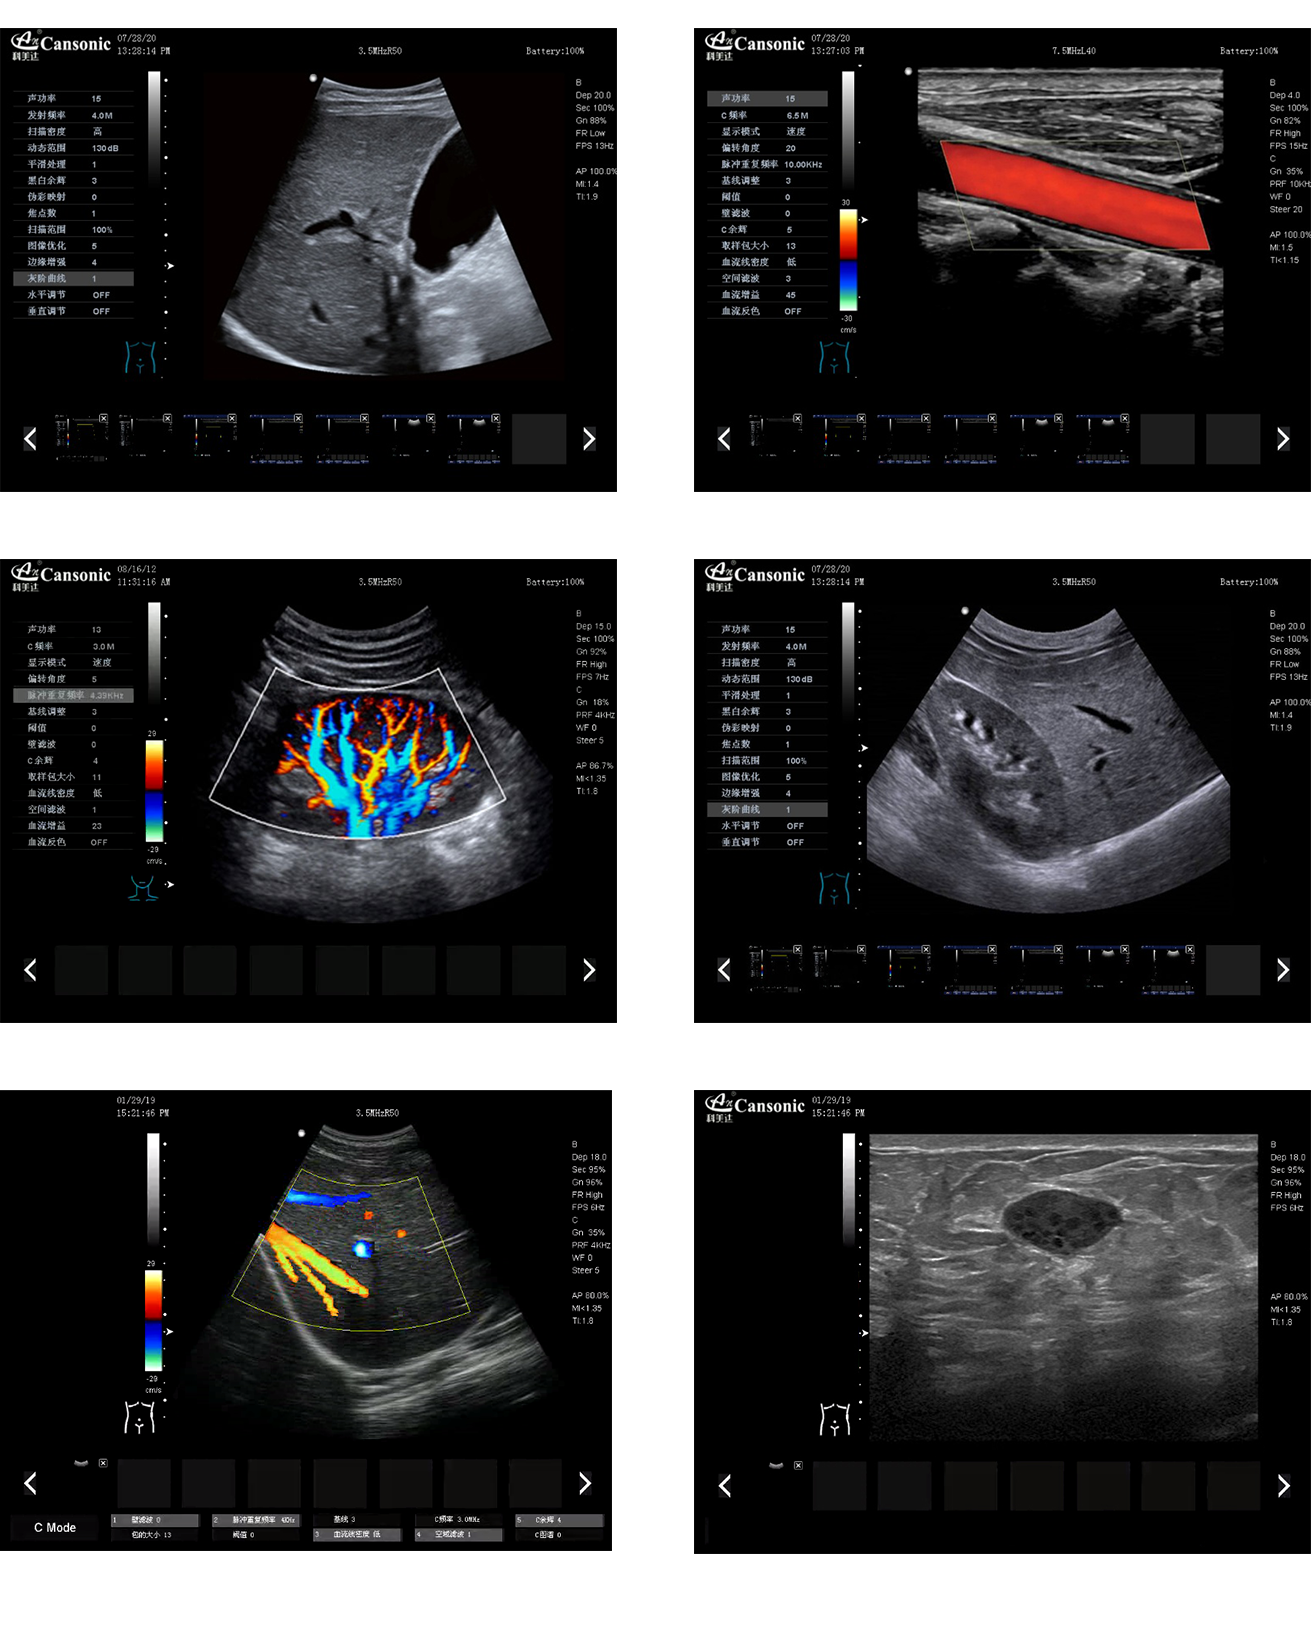

科美達K8圖像實例

1、全新一代便攜彩超,采用高端彩超技術,提供完整的臨床解決方案,適應各種臨床環(huán)境

2、圖像細膩,質量優(yōu)異,同時性能穩(wěn)定,每天能做大量檢查

3、選擇手動或自動包絡頻譜,一鍵顯示各種血流動力學數(shù)據

4、高分辨率灰階血流成像,明顯提升對微細血管的血流探測能力,對大血管管壁成像及管壁斑塊的診斷有著很大幫助